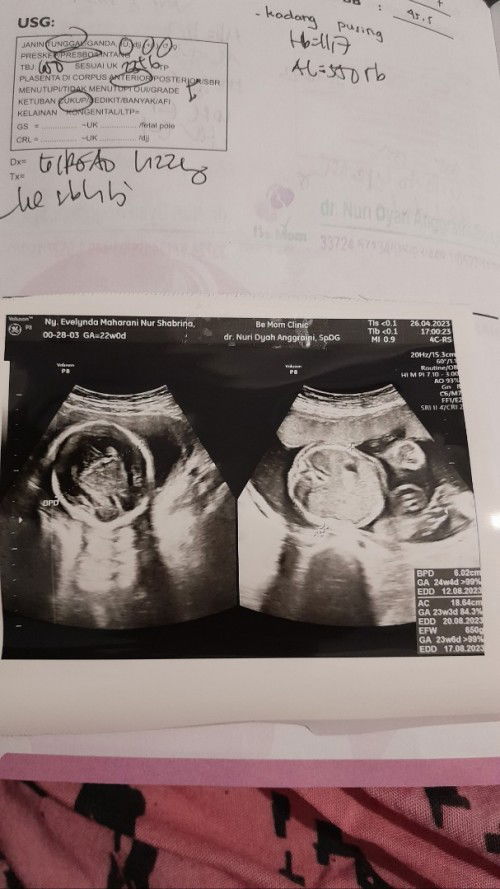

Gestational Age yang bener yg mana

Bun mau tanya itu usia kandungan sy yg bner yg mana kok banyak bgt GAnya. Klo dari usg bulan lalu sih harusnya hari ini udh 24 minggu, tapi USG hari ini beda lagi sy bingung. Dokter bilangnya usia kandungan sy 5 bulan. Tapi hpl 17 agustus. Mksd saya mau saya sesuaikan berapa minggunya biar bisa saya pantau di aplikasi asianparent ini bun. Mohon pencerahannya makasih. #seriusnanya #bantusharing #ingintahu #firstmom #pleasehelp #firstbaby